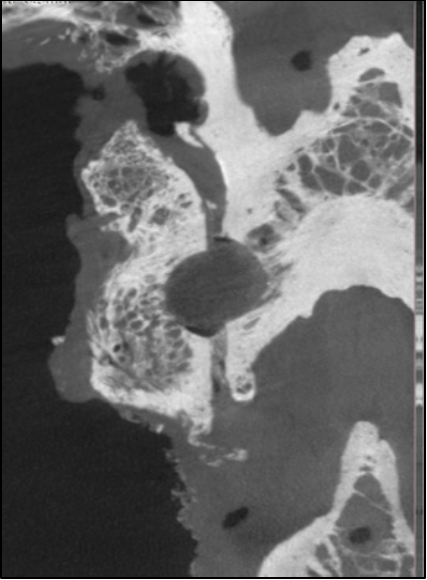

Efficient, repeatable method maximizes the decorticated surface area inside the facet joint

Burring can be inconsistent and limited to the facet joint line

Fuse

NorthStar Facet Fusion

Robust fusion through the facet joint on

6-month post-op CT

Standard of Care

Standard facet burring and eggshell-like fusion over the facet joint